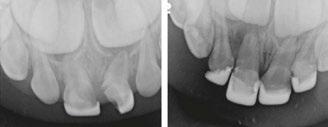

Several clinical solutions exist for primary anterior teeth with multisurface decay. Full coronal restoration of carious primary incisors may be indicated when caries is present on multiple surfaces, pulpal therapy is indicated, caries may be minor, but oral hygiene is very poor, or in a child with severe early childhood caries or a high caries risk diagnosis.1 Depending on the clinical scenario, a minimally invasive approach with the utilization of a high viscosity glass ionomer cement (HVGIC), with or without the combination of silver diamine fluoride (SDF) in a strip crown form, may pause the caries progression and provide an adequate clinical solution. Resin composite strip crowns have shown 80% retention rates and adequate parental satisfaction,1-4 although composite resin strip crowns have shown lower retention rates in teeth with decay involving three or more surfaces and particularly in children with a high caries risk4-6 (Figure 1). This could be from the continued high caries risk behaviors of the patient, as composite resin strip crowns in this population have shown to have increased inflamed marginal gingiva and gingival bleeding, increased plaque retention along the restoration, and loss of some restorative material.5,6

2: NuSmile® Anterior Zirconia crowns at 2-year follow up. Note the high amount of plaque accumulations along the untreated cuspid and existing stainless-steel crowns

A 2-year-old male who received full mouth dental rehabilitation (FMDR) under general anesthesia presented for his 6-month recall at 2-year post FMDR. He had significant plaque accumulations with poor oral hygiene along his existing stainless-steel crowns (SSCs) and non-treated teeth. Additionally, the patient had gingival bleeding and gingival inflammation

Figure 1: Occlusal films at recall visit in high caries risk patients showing loss of material and recurrent decay in composite resin strip crowns Figure

around these clinical sites. His anterior zirconia crowns showed healthy gingival margins with little-to-no plaque accumulations. This positive clinical finding is from the highly polished nature and biocompatibility of pediatric zirconia crowns. These restoration features limit plaque accumulations on the restoration and along the marginal gingiva, providing a localized positive aspect directly related to the choice of restorative material (Figure 2).

Case 2

A 3-year-old female presented with pulpal necrosis and abscess on #E and pulpal necrosis on #F. Extraction therapy or pulpectomy was offered. The family was highly motivated to retain #E and #F. The pulpectomy was performed with 0.02 K-Flex hand files, 3% NaOCl with a lateral vented needle, obturated with Vitapex (Neo Dental International Inc., Federal Way, Washington), a premixed paste of calcium hydroxide and iodoform. The access was filled with a HVGIC sealing the pulp therapy and increasing the clinical success by minimizing the potential for bacterial contamination. NuSmile ZR anterior crowns were selected as offering a full-coverage, esthetic, cemented restoration with no polymerization shrinkage when compared to a composite restoration. Crowns were cemented with NuSmile® BioCem (NuSmile, Houston, Texas). This is clinically beneficial as the provider would want to cement a restoration that provides limited microleakage minimizing the potential for bacterial contamination.15-17 At 6-month follow up, lesion healing had occurred with healthy gingival margins and no plaque accumulations (Figure 3).

A 4-year-old female presented with existing Silver Modified Atraumatic Restorative Technique (SMART) style restorations on #D, #E, #F, #G, and caries on other teeth. These anterior lesions

had been previously treated using SDF and covered with a HVGIC in a strip crown form. Though her lesions were stable from the clinical success of the SDF and HVGIC, these restorations were starting to fracture and demonstrate loss of material. The family wanted a more esthetic treatment option that would have a longer survivability. Additionally due to her high caries risk nature, a full coverage restoration with NuSmile® ZR anterior crowns were a more ideal solution in stabilizing her extensive decay pattern and covering staining from SDF therapy (Figure 4).

Figure 3: NuSmile® ZR Crowns were selected as a cementable full coverage restoration. At 6-month recall, apical tissues were healed with excellent gingival health Figure 4: SMART style restorations that were definitively restored with NuSmile® ZR Crowns as an esthetic option to cover SDF staining